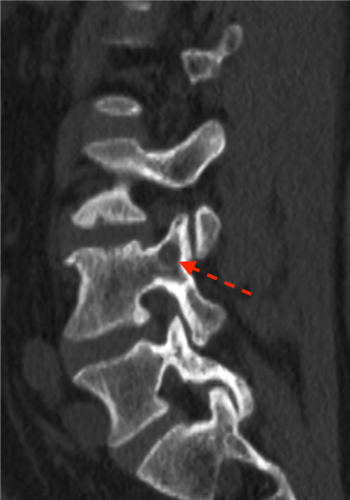

结合樊先生核磁共振(MRI)等相关的检查结果,医生发现樊先生的腰3/4节段左侧椎间盘巨大突出,并脱出游离至腰4椎体后缘,将脊髓神经严重挤推至右侧,这也是造成樊先生明显的腰腿痛的原因。针对这种高度游离脱出的腰椎间盘突出症,以往常采用椎板部分切除、甚至腰椎融合术,手术创伤大、风险高、费用高。重医附二院楚磊教授、石磊医师、于庆帅医师及护理团队进行了缜密的讨论与研究,和樊先生详细沟通后,决定行经皮内镜手术来治疗他的腰椎间盘突出症。

正是在如此强大的技术支撑之下,樊先生的手术顺利进行。术中,医生精确定位患者腰椎病灶节段,只通过皮肤不足1cm的切口,在椎弓根开了一个小孔,将脱出压迫神经的髓核组织成功摘除。

术前术后对比,及术中椎体环锯成形术影像